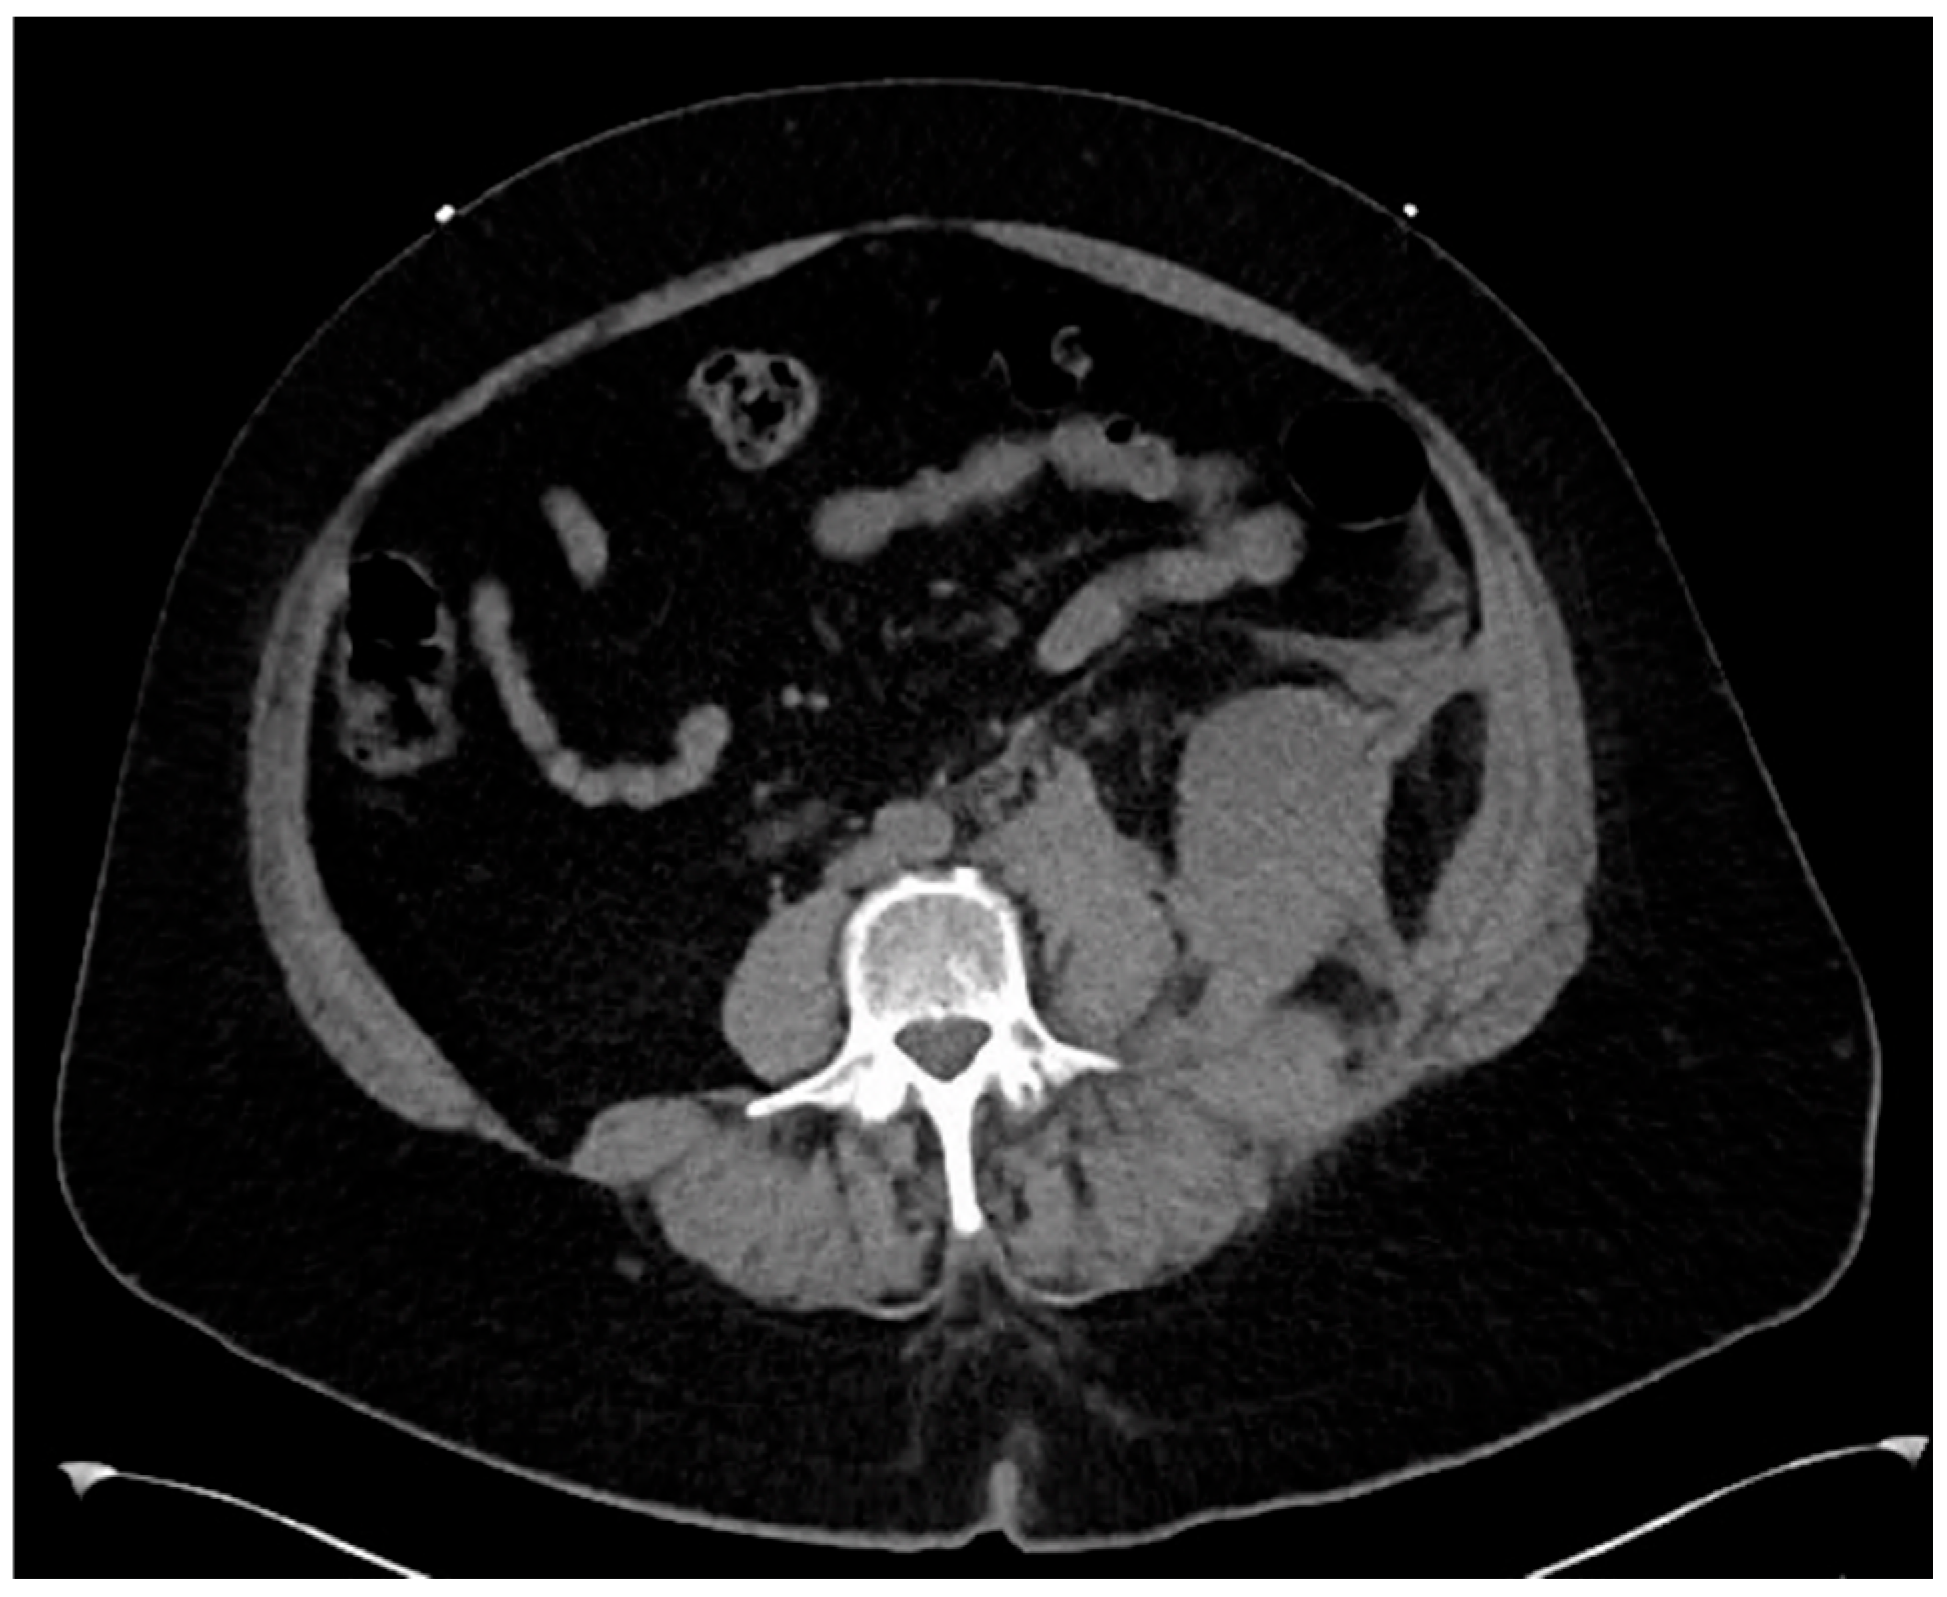

Computed tomography angiogram (CTA) protocol images are displayed below. Figure 1 and Figure 2 correspond to her state prior to tPA administration; notice the 100% occlusive aortic thrombus. Figure 3 and Figure 4 are post-tPA administration, demonstrating the fully restored aortic flow.

Figure 1. CTA in transverse view prior to tPA.

The patient’s only complaint was that both of her legs hurt and she could not feel them. On initial examination, the patient’s initial vital signs were as follows: blood pressure: 120/44; heart rate: 53; respiratory rate: 20; rectal temperature: 93.3 F. Her lower extremities showed bilateral petechiae and molting of the feet and were cold to the touch. Dorsalis pedis pulses and posterior tibialis pulses were unable to be palpated. These absent pulses were verified using bedside Doppler and color-flow ultrasound. The patient was immediately brought to imaging, and a CT angiogram of the aorta with a contrast protocol was performed to rule out dissection. CT imaging demonstrated an occlusion of the distal abdominal aorta (without dissection), with concurrent occlusion of the bilateral common iliac arteries.